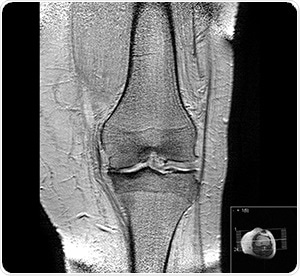

Knee osteoarthritis stages II and III by Harrygouvas at Greek Wikipedia. [CC BY-SA 3.0 or GFDL 1.3], from Wikimedia Commons

Osteoarthritis is a common degenerative condition. It is characterized by the diminution of cartilage in and around the joints which results in pain and loss of mobility. Age is seen to be the most common cause of osteoarthritis, but, traumatic joint injury can also cause joint degeneration in people of all ages. The progression of the condition can be slowed and symptoms can certainly be managed, however the underlying causes that lead to the development of this condition cannot be reversed.